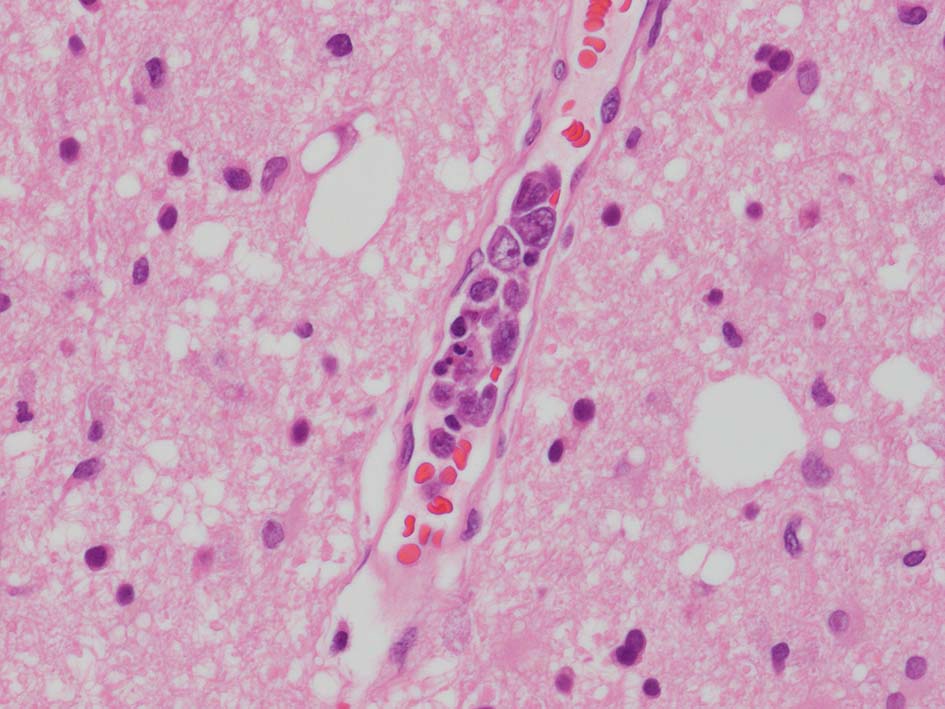

脳梗塞病変の脳生検組織

梗塞組織近傍の細血管内に腫瘍細胞が認められる.

脳;くも膜下腔の小動脈内, 脳白質の細血管内に腫瘍細胞が充満している。